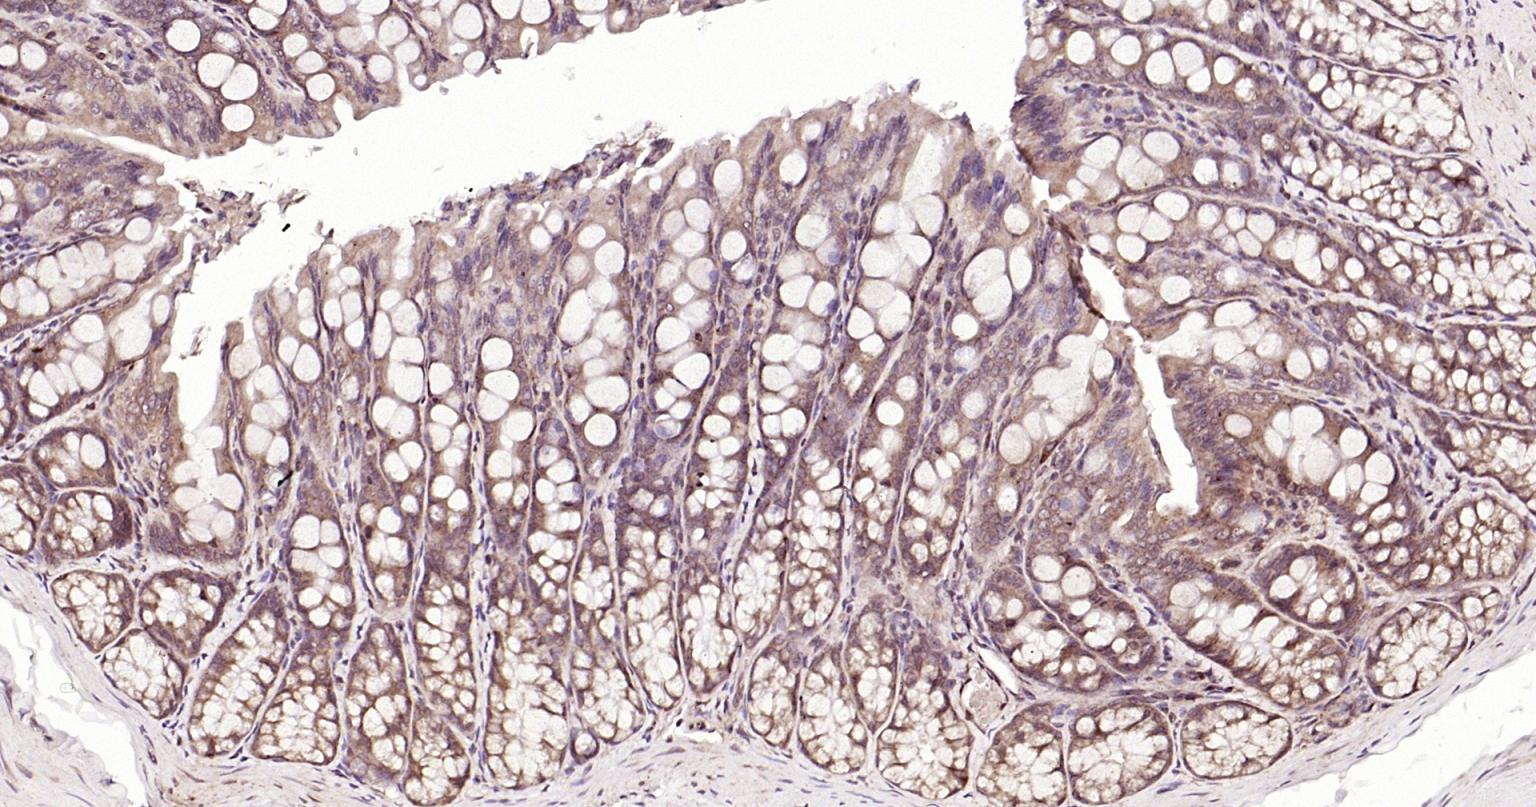

| IHC-P | Human, Mouse, Rat | Rabbit | 1:400-800 |